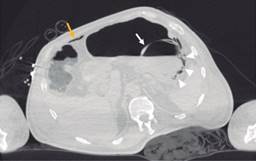

Paciente masculino de 69 años de edad con historia de diabetes mellitus tipo 2 en tratamiento con metformina y clorpropamida, hipertensión arterial en tratamiento con losartán y amlodipino. Se presenta al servicio de urgencias por mostrar cefalea, dolor torácico, tos, mialgias, artralgias y disnea de una semana de evolución. A su ingreso muestra frecuencia cardiaca 114 lpm, frecuencia respiratoria de 24 rpm, saturación de oxígeno de 80% sin apoyo de oxígeno suplementario, glucosa 587 mg/dl, leucocitos de 25,690 cel/mm3, neutrófilos 85%, linfocitos 1.2%, hemoglobina 16.3 g/dl, procalcitonina 3.78 ng/dl, gasometría arterial con pH 7.41, pCO2 21 mmHg, PO2 35 mmHg, HCO3 13 mmol/l, saturación de oxígeno 62%. Se realiza prueba rápida de antígeno para SARS-CoV-2 resultando positiva, tomografía axial computarizada (TAC) de tórax en la que se observan datos radiológicos sugestivos de infección por SARS-CoV-2 (Figura 1), se inicia manejo con oxígeno suplementario, bomba de infusión de insulina, carbapenémicos, antihipertensivos, dexametasona y profilaxis antitrombótica con enoxaparina. A las 48 horas de su ingreso continúa con choque séptico, se inician aminas vasopresoras, se realiza intubación orotraqueal y soporte con ventilación mecánica invasiva, se coloca sonda nasogástrica (SNG), la cual 24 horas posterior a su colocación reporta hematemesis acompañada de distensión abdominal, leucocitosis de 40,000 cel/mm3, se realiza TAC abdominopélvica simple, la cual revela neumatosis gástrica y neumoperitoneo (Figura 2), se efectúa laparotomía exploradora urgente encontrando necrosis de la curvatura mayor del estómago, se lleva a acabo gastrectomía vertical con engrapadora GIA cartuchos morados de 45 y 60 mm (Figura 3), se refuerza línea de grapeo con sutura continua prolene 00, se coloca sonda de yeyunostomía de alimentación a 60 cm del ángulo de Treitz y se dejan drenajes tipo Saratoga. A las 24 horas postoperatorias paciente reporta estabilidad hemodinámica y se suspenden aminas vasopresoras, se inicia nutrición enteral con dieta elemental. El quinto día postquirúrgico muestra adecuada tolerancia a dieta enteral por yeyunostomía, se realiza prueba con azul de metileno por SNG sin evidencia de fugas y descenso de leucocitos a 24,000 cel/mm3. Se recaba resultado de histopatología, el cual revela necrosis panmural asociada a trombosis arterial secundaria a microorganismos compatibles con Mucor sp., por lo que se inicia manejo con anfotericina B (Figuras 4 y 5). En el seguimiento muestra buena evolución, se realiza TAC abdominopélvica con contraste por SNG, la cual descarta fugas y colecciones intraabdominales y se corrobora integridad de la pared gástrica, se retiran drenajes y se da alta de cirugía general el día nueve postquirúrgico continuando manejo a cargo del servicio de medicina interna. Durante los siguientes días de hospitalización, el paciente presenta deterioro cardiovascular y pulmonar, se toma urocultivo, el cual evidencia crecimiento de Candida tropicalis, se realiza TAC de cráneo, tórax y abdominopélvica con contraste oral (Figuras 6 y 7), continúa sin evidencia de fugas a nivel abdominal, se descarta mucormicosis rinocerebral y pulmonar, se reporta probable neumonía bacteriana sobreañadida y neumopatía intersticial secundaria a COVID-19, persiste deterioro clínico y choque refractario, el paciente fallece a 29 días de su ingreso.